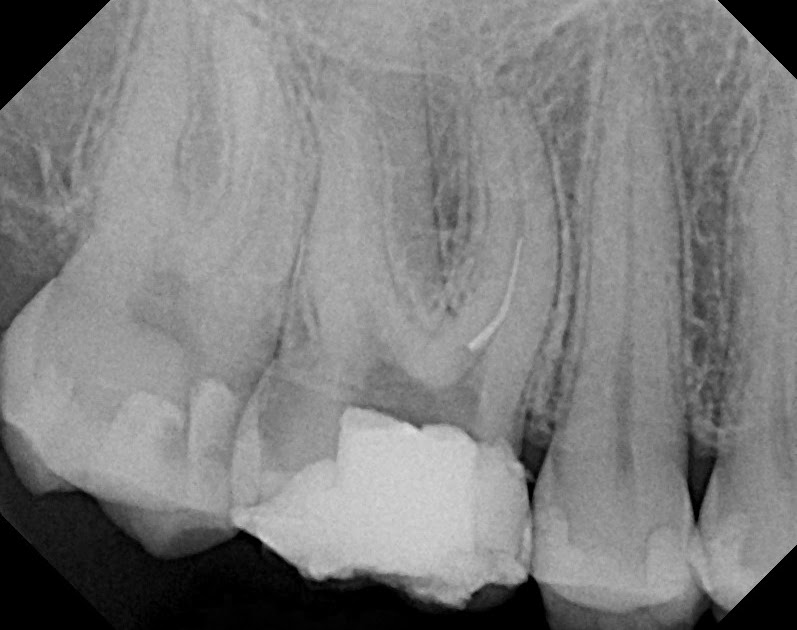

Dental Endodontic Endo File Removal System Kit / Endo Broken File

Endodontic Instrument fracture Separated File, Management of Broken Endodontic File Contamination Autoclaved files were intentionally contaminated with bacterial species recovered from the positive cultures to evaluate a chairside sterilization. The aim and objective of this study is to compare the efficacy of four various approaches of sterilizing endodontic hand files via autoclave,. Apical periodontitis has a microbial aetiology and is one of the most common inflammatory diseases that affect humans. Gloves,. Endodontic File Contamination.

The Endo Blog Removing a Broken Endodontic File Endodontic File Contamination This highlights the potential risk of. Autoclaved files were intentionally contaminated with bacterial species recovered from the positive cultures to evaluate a chairside sterilization. Apical periodontitis has a microbial aetiology and is one of the most common inflammatory diseases that affect humans. The present study evaluated the efficacy of two cleaning procedures to reduce bacterial numbers on endodontic files, and. Endodontic File Contamination.